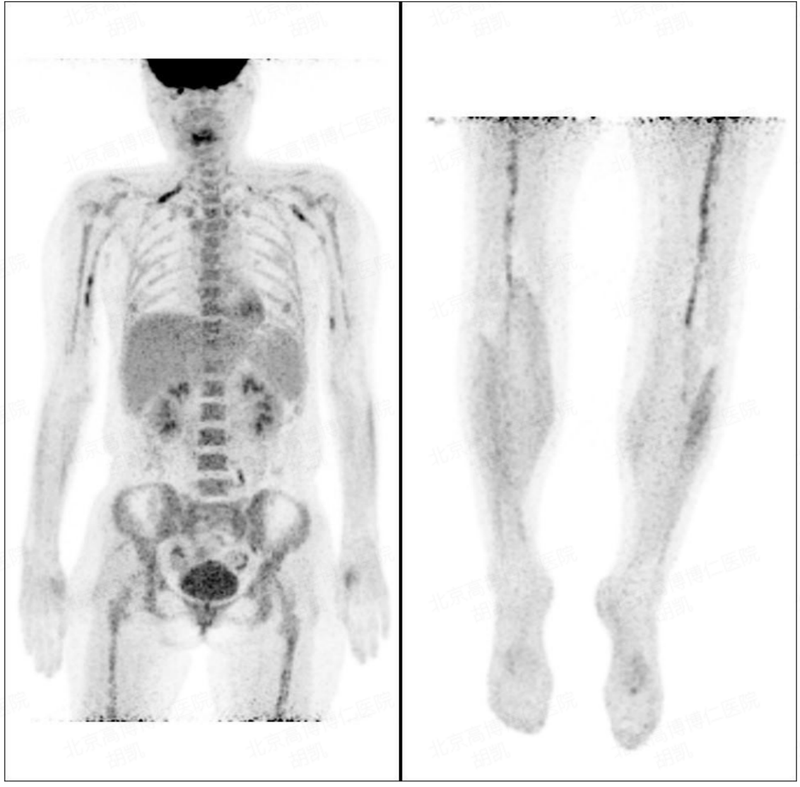

小汪(化名)感到身體不適是在2年前(2021年2月),起初只是感到頭暈乏力,逐漸加重。當時以為是貧血,只是在家附近的醫(yī)院做了一項血常規(guī)的檢查,結(jié)果僅顯示白細胞輕度升高(白細胞12.2610^9/L、血紅蛋白118g/L、血小板185x10^9/L),由于比較年輕(32歲),也沒有太當回事,于是未進一步深究。誰知半個月后,在原來乏力加重的同時,出現(xiàn)了持續(xù)的發(fā)熱,體溫常在38度左右徘徊,感冒藥,抗生素均無效果。再次前往醫(yī)院就診,復查血常規(guī),才發(fā)現(xiàn)問題嚴重,這時的白細胞升高,超過正常值的5倍:50.9210^9/L。同時還發(fā)現(xiàn)了貧血(血紅蛋白96g/L)、血小板減少(5410^9/L);更令人不安的是在血液中發(fā)現(xiàn)了60%的異常淋巴細胞。當?shù)蒯t(yī)生考慮急性白血病的診斷,立即安排入院完善骨穿等一系列檢查。檢查結(jié)果提示,患者骨髓里果然存在大量異常淋巴瘤細胞(90%),并根據(jù)免疫學,細胞遺傳學,分子生物學等詳細的檢測,確定診斷為:伯基特細胞淋巴瘤/白血病。伯基特淋巴瘤(Burkittlymphoma)是一種侵襲性極強的B細胞淋巴瘤,增殖速度極快。它常見于兒童和青少年,比較罕見,只占成人非霍奇金淋巴瘤的1%至2%。這種高度惡性的淋巴瘤往往可以短時間內(nèi)侵襲全身多個組織器官。小汪住院后的檢查也發(fā)現(xiàn),淋巴瘤來勢洶洶,短短一個月的時間,已經(jīng)播散到骨髓,肝臟,脾臟(PET/CT檢查發(fā)現(xiàn)),乃至中樞神經(jīng)系統(tǒng)(腰穿檢查,腦脊液中發(fā)現(xiàn)腫瘤細胞11.4%)。伯基特淋巴瘤一旦確診,應(yīng)該盡快開始化療,這種高度侵襲性的淋巴瘤往往初期對化療也是高度敏感的。伯基特淋巴瘤的化療和常見的彌漫大B細胞淋巴瘤有所不同,目前更傾向使用強度更大的高劑量化療方案,因為此類方案首先在兒童患者中取得了很好的療效,使兒童伯基特淋巴瘤的化療治愈率超過80%。小汪確診后,在首診醫(yī)院采用了高劑量的R-Hyper-CVAD(A/B)方案交替的化療,5個療程。化療雖然艱苦,好在年輕,既往身體也不錯,5個高強度化療也算順利扛了下來。在每個化療之前,都進行了療效評估。好的一方面是,一個療程之后,小汪骨髓中的腫瘤細胞從90%降至為0,但另一方面的結(jié)果卻令人沮喪,腦脊液里的腫瘤細胞總是不能清除,隨著腦脊液的病情長時間無法緩解,小汪開始出現(xiàn)了一系列的神經(jīng)系統(tǒng)癥狀,從雙下肢疼痛無力,到左眼無法閉合,再到雙手和肩膀的麻木疼痛。復查的PET/CT也提示:雙側(cè)頸根部、腋窩、雙上肢、左側(cè)腰大肌后方、雙側(cè)大腿及左側(cè)腘窩神經(jīng)走行區(qū)代謝活性增高,為淋巴瘤神經(jīng)浸潤。據(jù)此,當?shù)蒯t(yī)生考慮小汪為復發(fā)難治型伯基特淋巴瘤,治療陷入僵局。為了尋求進一步治療,小汪來到我科就診。正如我們之前提到過伯基特淋巴瘤的治療是要求“一擊而中”的,抓住早期腫瘤對化療比較敏感的時期,連續(xù)高劑量短療程的化療,力爭達到完全緩解,隨后不能放松,進行強化鞏固化療,從而大多數(shù)患者可能獲得治愈。然而有些患者,存在多種預(yù)后不良因素,或者受年齡體力限制不能耐受充分的化療,或者化療劑量療程不規(guī)范等,導致化療不能完全緩解,成為少數(shù)復發(fā)或難治型。這類患者預(yù)后極差,長期生存概率不到20%。小汪入我院后,我們完成了一些評估,我們看到小汪存在以下主要的不良因素,可能與其化療效果不佳有關(guān)。首先,發(fā)病過程類似白血病,骨髓中存在大量腫瘤細胞,廣泛累及全身;其次,患者中樞神經(jīng)系統(tǒng)及周圍神經(jīng)均存在腫瘤細胞,中樞神經(jīng)系統(tǒng)和血液之間存在的天然屏障(血腦屏障)阻擋了化療藥物的一部分作用。此外,我們的檢查發(fā)現(xiàn),小汪的腫瘤還存在TP53基因突變,也是最常見的預(yù)后不良的基因特點。由于中樞神經(jīng)系統(tǒng)受累及的成人伯基特淋巴瘤患者的治療方案并無統(tǒng)一標準,復發(fā)難治階段的治療更是無據(jù)可循,我們只能根據(jù)小汪疾病的以上特點,再結(jié)合我們既往診治復發(fā)難治伯基特淋巴瘤的經(jīng)驗教訓,來制定整體的治療策略:先采用化療聯(lián)合CART細胞治療技術(shù),突破化療耐藥,爭取達到完全緩解,再采用異基因造血干細胞移植治療進行鞏固,來爭取治愈的機會?;熾A段,我們考慮到患者對既往方案有一定的療效,只是中樞神經(jīng)系統(tǒng)緩解不理想,我們相對保守的采用了原來的化療方案的主體用藥,大幅提高了以中樞作用為主的甲氨蝶呤的用藥劑量,同時加入了噻替哌——另一個能穿透血腦屏障的藥物?;焺偨Y(jié)束時小汪的神經(jīng)痛的確得到了很好的緩解,似乎讓我們看到了希望。沒想到,化療后的半個月,隨著血象的回升,癥狀再次出現(xiàn)。這種情況在耐藥的伯基特淋巴瘤中非常常見,面對化療的打擊,腫瘤的恢復速度已經(jīng)超過了身體正常細胞的恢復速度,提示化療方案失效。PET/CT檢查證實了這個不好的結(jié)果。這次挽救性化療的失利,對小汪和我們都是一次打擊。好在小汪是個樂觀的姑娘,家人也全力支持和鼓勵患者。患者及家屬對我們充分信任,加之雖然腫瘤余孽未凈,然而腫瘤負荷并不算高,我們還有機會。第二次化療,我們徹底放棄了原有的化療方案,嘗試了Pola-ICE聯(lián)合靶向藥物的新化療方案,考慮到化療療效的不確定性,后續(xù)治療機會可能稍縱即逝,于是在化療的同時,我們就積極準備了CD19-CART細胞的制備。化療結(jié)束時,小汪的癥狀再次緩解一些。這次我們沒有給腫瘤喘息的機會,化療結(jié)束后就進行了CD19-CART細胞的回輸。隨著CART后的發(fā)熱(CRS反應(yīng)1級),小汪四肢神經(jīng)疼痛反而加重,不過以我們的經(jīng)驗判斷,這次的疼痛加重可能與CART治療的局部炎性水腫反應(yīng)有關(guān)。果然隨著CART反應(yīng)的逐漸平息,疼痛也逐漸緩解。CART后1個月復查,不僅腦脊液檢查腫瘤細胞已經(jīng)陰性,而且PET-CT結(jié)果也令人鼓舞,小汪迎來了患病以來的首次完全緩解!此時小汪與腫瘤的斗爭已持續(xù)進行了近8個月。盡管這次化療聯(lián)合CART獲得了前所未有的療效,但是CART治療伯基特淋巴瘤的經(jīng)驗在世界范圍內(nèi)也并不多。一次CART治療是否能夠達到長期的緩解甚至治愈疾病,尚屬未知。不過我們的既往經(jīng)驗和教訓提示,對于復發(fā)難治的伯基特淋巴瘤,特別是伴有中樞神經(jīng)累及的患者,一次CART治療后仍有很高的復發(fā)率,而且CART后復發(fā),無疑會面臨巨大的治療困難。因此,我們居安思危,在目前完全緩解的情況下,采用了異體造血干細胞移植的鞏固治療方式。為了進一步提高緩解深度,我們在移植預(yù)處理中加入了供者來源的雙靶點CART。由于供者為全相合的同胞供者,移植過程非常順利,造血如期恢復,小汪順利出倉。移植后的1個月,2個月的PET/CT及骨穿,腰穿都一切安好,持續(xù)保持完全緩解。原本以為,只要后續(xù)按部就班的復查和調(diào)整移植后用藥,小汪的病情就會穩(wěn)定,隨著時間的推移,逐漸走向治愈。然而,始料未及的是在移植后的第三個月,小汪再次出現(xiàn)了腿痛??紤]到伯基特淋巴瘤有快速進展的特點,我們提前了PET/CT的復查,結(jié)果令人大受打擊:盆腔左側(cè)壁不規(guī)則軟組織腫塊,與骶管、腹膜及相鄰盆壁軟組織分界不清,范圍約為9.9×4.4cm,SUVmax為21.4;左側(cè)肱骨中段、左側(cè)脛骨中段、右側(cè)脛骨平臺、雙側(cè)股骨下段、雙側(cè)第9肋骨、右側(cè)第7肋,SUVmax為24.3;右側(cè)頸部、右側(cè)鎖骨,與神經(jīng)走形分布一致,長徑約為3.3cm,SUVmax為17.2。左側(cè)腹壁皮下數(shù)個結(jié)節(jié),直徑約為0.8cm,F(xiàn)DG攝取增高,SUVmax為16.4;左側(cè)臀部及大腿后側(cè)肌肉增厚形成腫塊,范圍約為35.3×7.7cm,SUVmax為20.0;歷經(jīng)多次化療,2次CART,外加異基因造血干細胞移植,這么快就大面積復發(fā)。當時我們和患者家屬的心態(tài)都跌至冰點,一度“建議放棄治療”的念頭縈繞在我們治療組的醫(yī)生心里。反倒是小汪和家人堅持的信念鼓勵了我們醫(yī)生。面對信任和堅持,我們和小汪一起重新振作,再次開始整理思路,分析病情。首先我們對病灶重新進行了穿刺,病理提示可以作為治療靶點的腫瘤標記依然是陽性,包括:CD20(90%+),CD19(90%+),CD22(80%+),CD79b(90%+),CD30(80%)。而腦脊液和骨髓依然保持緩解,沒有腫瘤細胞?;颊弋愺w移植后3個月,身體狀態(tài)還沒有完全恢復,并且移植前表現(xiàn)出化療療效有限,因此,移植后我們不進行大劑量化療,仍然把重點放在對身體損傷相對較小的靶向及免疫治療上:首先進行了一療程的Pola聯(lián)合苯達莫斯汀為主的低劑量化療聯(lián)合靶向藥物,來控制快速進展的腫瘤,同時也可作為CART前的預(yù)處理。與此同時,為了造血能快速恢復,化療后進行了一次供者造血干細胞的輸注。這次化療還算順利,化療后原本計劃回輸供者來源的CD20-CART,誰知在回輸前患者又感染了新冠病毒,回輸計劃只好推遲。經(jīng)過20余天的抗新冠病毒的治療,新冠轉(zhuǎn)陰,并且這次的靶向化療也很好的抑制了腫瘤的發(fā)展。我們再次給予一次類似方案的化療,隨后回輸了CD20-CART。由于CART來源是健康的供者,加之這次的CART治療前我們已經(jīng)停止了抗排異的免疫抑制藥物,所以此次CART細胞充分發(fā)揮了抗腫瘤的作用,患者CART回輸后無論從CART細胞的擴增檢測,還有CART治療相關(guān)的發(fā)熱等反應(yīng),都遠強于前兩次的CART治療。這次CART治療過程中,全血減少,新冠病毒反復激活,持續(xù)的高熱等CRS反應(yīng),給治療帶來了重重風險。我們綜合處理CART后不良反應(yīng)的經(jīng)驗、小汪的堅強以及家人的悉心照顧,在眾人合力下終于幫助小汪安全度過了這段最艱難的時光。這次移植后的聯(lián)合治療也取得了超預(yù)期的療效:巨大的腫瘤負荷居然再次消失,PET/CT:再次達到完全緩解!從前次復發(fā)中我們意識到,伯基特淋巴瘤的復發(fā)可以非常迅速,單純像PET/CT這樣的影像學評估,很可能不能及時發(fā)現(xiàn)早期復發(fā)。于是我們在后續(xù)的監(jiān)測中采用了采血進行ctDNA的檢測。對患者腫瘤特有的4個基因位點進行靶向的追蹤。也確實在一次檢測中發(fā)現(xiàn)了Myc突變的ctDNA轉(zhuǎn)陽,隨后我們用Pola進行了一次搶先的靶向治療,ctDNA再次轉(zhuǎn)陰。在此后的監(jiān)測隨訪的1年中,患者始終保持著完全緩解狀態(tài)。我們也一直保持高度的警惕,繼續(xù)努力為患者保駕護航。我們每年要接診治療數(shù)百例復發(fā)難治的惡性淋巴瘤和骨髓瘤患者,其中難度最大的淋巴瘤類型要屬復發(fā)難治的伯基特淋巴瘤。如果患者復發(fā)時存在大包塊,胃腸道大腫塊,中樞神經(jīng)系統(tǒng)受累,骨髓及血液中大量腫瘤細胞等情況的話,治療難度極大。我們有成功的經(jīng)驗,也有失敗的教訓。不過隨著醫(yī)學的進步,可以用來治療這類極其困難的患者的療法和藥物也越來越多。這例患者診治過程中使用了高劑量化療、新的抗體耦聯(lián)ADC類藥物、自體CART細胞治療、異體造血干細胞移植、供者來源CART細胞治療,腫瘤組織基因二代測序,血液ctDNA檢測等等診斷治療方法。這些新的技術(shù)和療法,為這類患者帶來了新的希望。當然,除了這些醫(yī)學技術(shù)以外,我們也看到,在病情曲折反復,療效出現(xiàn)挫折和失敗的至暗時刻,患者的堅強意志,家人的陪伴支持,醫(yī)患的信任合作,才能在黑暗中窺見曙光,在堅持中發(fā)現(xiàn)希望。